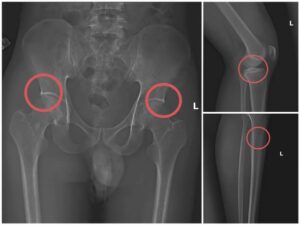

Đáng chú ý, Châu trực tiếp thực hiện hành vi tiêm thuốc mê rồi dùng kim tiêm, búa, đinh tác động vào xương người mua bảo hiểm, tạo nên các vết nứt, vỡ xương tương tự tai nạn thật. Khi thương tích đã tạo xong, Châu tiếp tục hướng dẫn các đối tượng dựng hiện trường giả như điện giật ngã, trượt chân ngã suối, nhằm hợp thức hóa bệnh án và hoàn thiện hồ sơ yêu cầu chi trả.

Hiện trường các đối tượng gây mê và can thiệp xương.